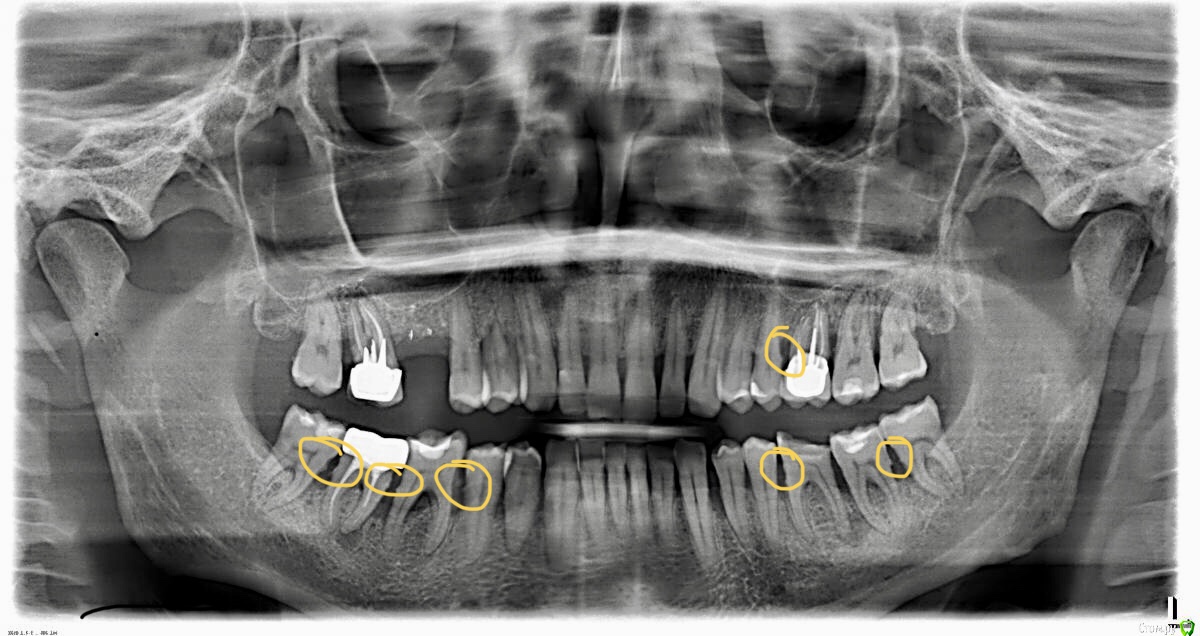

stommm Опубликовано 3 октября, 2019 Поделиться Опубликовано 3 октября, 2019 (изменено) Консервативное лечение это дохирургический этап. SRP. Надо механически (ультразвук, кареты, боры) насколько это возможно убрать все отложения из-под десны и сгладить поверхность корня. То, что я обвёл на Вашей ОПТГ. Хирургия после оценки результата при условии что консервативно уже ничего не сделать. И только на фоне удовлетворительного уровня индивидуальной гигиены. Вообщем начинайте с этого. Гигиенисты обычно под десну инструментом не заходят, и вам нужна не просто профгигиена. Изменено 3 октября, 2019 пользователем stommm Ссылка на комментарий